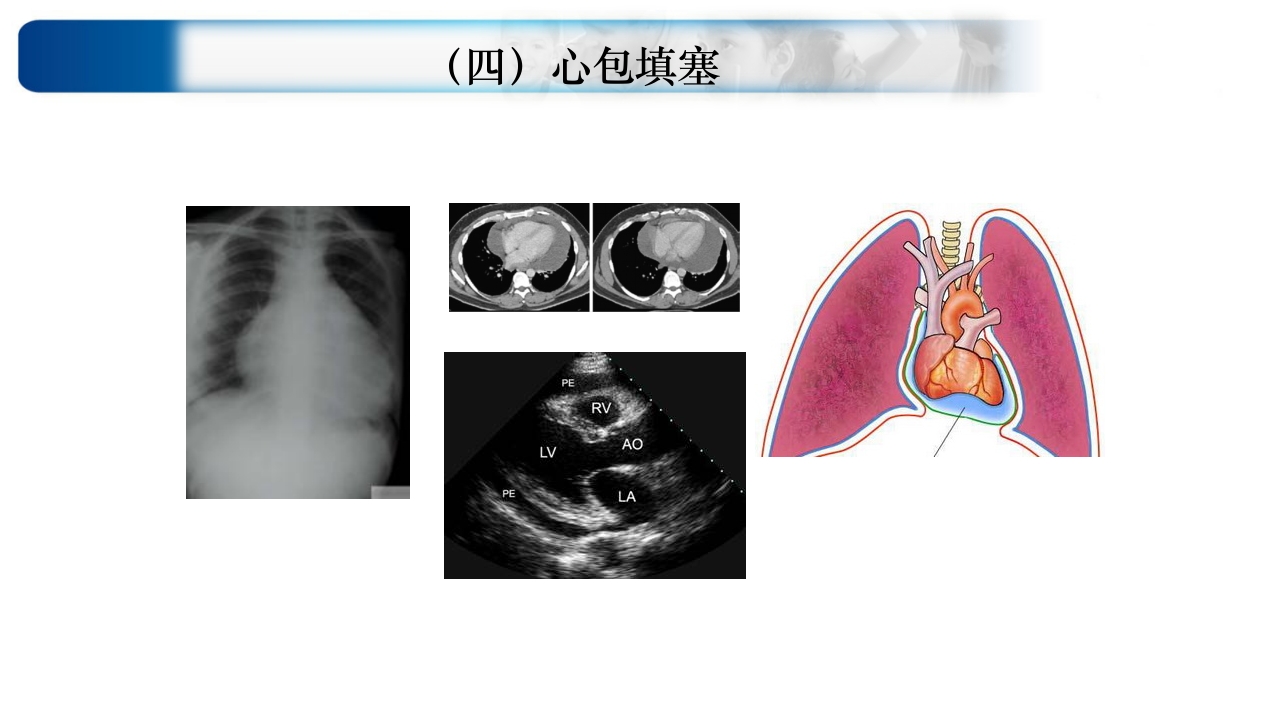

心源性休克(CS) 一 休克概念及内涵 由多种原因引起的 以有效循环血容量减少、 组织灌注不足、 细胞代谢紊乱和功能受损 为主要病理生理改变的综合征 是血压下降? 维持有效循环血量:三个重要因素 休克发生的共同基础:有效循环血量减少 休克始动环节 二 心源性休克定义(广义/狭义) 心脏泵血功能衰竭 心输出量下降 导致有效循环血量明显下降 组织器官灌注急剧减少 组织缺氧及器官功能障碍 三 心源性休克诊断标准(3低1高) 临床表现 神志淡漠 皮肤苍白/紫绀 四肢冰冷 大汗淋漓 脉搏细数 尿量减少 ( 0.5ml/kg.h;2030ml/h) LAC增高 低灌注 重要体征 有创参数 血压下降 (SBP≤8090mmHg;ΔMAP下 降>30mmHg;Δ SBP> 60mmHg/30% PP<20mmHg...